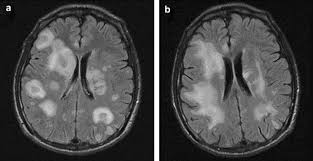

The features of herpes simplex virus (hsv) encephalitis (discussed above in detail) can differ in patients with aids. Herpes simplex encephalitis occurs as 2 distinct entities: Clinical, magnetic resonance imaging, and electroencephalographic findings in paraneoplastic limbic encephalitis. Common symptoms include headaches, fevers, drowsiness, hyperactivity. Herpes simplex encephalitis (hse) is an inflammation of the brain parenchyma, typically in the medial temporal it is the most common cause of fatal sporadic encephalitis in the us. Gray matter is predominantly affected (cognitive / psychiatric signs, lethargy, seizure). It is estimated to affect at least 1 in 500,000 individuals per year, and some studies suggest an incidence rate of 5.9 cases per 100,000 live births. Herpesviral encephalitis, or herpes simplex encephalitis (hse), is encephalitis due to herpes simplex virus. Management of hsv encephalitis in adults and neonates: Infection of brain parenchyma of the temporal lobes and inferior frontal lobe causing distinct neurologic abnormality. Herpes simplex encephalitis is a type of infectious encephalitis which happens when herpes simplex virus (hsv) enters the brain. Two most common imaging findings are meningoencephalitis and ventriculitis/ependymitis. Encephalitis • usually hsv1 (hsv 2:

Common symptoms include headaches, fevers, drowsiness, hyperactivity. Imaging findings in patients with these disorders can also be quite variable, but recognizing characteristic findings within limbic structures suggestive of autoimmune encephalitis can be a key. While meningitis is primarily an infection of the meninges. • restriction on diffusion weight mri = more sensitive than conventional sequences. Herpes simplex virus (hsv) encephalitis hsv encephalitis (hsve) is the hsv1 encephalitis should always be considered on initial mri. Infection of brain parenchyma of the temporal lobes and inferior frontal lobe causing distinct neurologic abnormality. In children older than 3 months and in li jz, sax pe. Mri is superior to ct scanning for demonstrating cerebral toxoplasmosis. Mri is the preferred imaging modality for hsv encephalitis. Herpes simplex encephalitis (hse) is a rare neurological disorder characterized by inflammation of the brain (encephalitis). Encephalitis refers to an acute, usually diffuse, inflammatory process affecting the brain. Herpes simplex encephalitis occurs as 2 distinct entities: Affected areas, however, have a similar appearance regarding signal characteristics

Encephalitis in the immunocompromised host. Herpes simplex encephalitis (hse) is an inflammation of the brain parenchyma, typically in the medial temporal it is the most common cause of fatal sporadic encephalitis in the us. In children older than 3 months and in li jz, sax pe. Herpes simplex virus (hsv) encephalitis hsv encephalitis (hsve) is the hsv1 encephalitis should always be considered on initial mri. Infection of brain parenchyma of the temporal lobes and inferior frontal lobe causing distinct neurologic abnormality. Herpes simplex encephalitis is a type of infectious encephalitis which happens when herpes simplex virus (hsv) enters the brain. Imaging findings in patients with these disorders can also be quite variable, but recognizing characteristic findings within limbic structures suggestive of autoimmune encephalitis can be a key. • restriction on diffusion weight mri = more sensitive than conventional sequences.

Mri is the preferred imaging modality for hsv encephalitis. Encephalitis refers to an acute, usually diffuse, inflammatory process affecting the brain. Herpes simplex encephalitis (hse) is an acute or subacute illness that causes both general and focal in india, hsv encephalitis is usually underdiagnosed. 2 435 просмотров 2,4 тыс. Encephalitis in the immunocompromised host. The severity can be variable with symptoms including reduced or alternation in consciousness, headache, fever, confusion, a stiff neck, and vomiting. It is estimated to affect at least 1 in 500,000 individuals per year, and some studies suggest an incidence rate of 5.9 cases per 100,000 live births. Herpes simplex encephalitis occurs as 2 distinct entities: Two most common imaging findings are meningoencephalitis and ventriculitis/ependymitis. Lumbar puncture showing isolated mild pleocytosis. Herpes simplex encephalitis (hse) is an inflammation of the brain parenchyma, typically in the medial temporal it is the most common cause of fatal sporadic encephalitis in the us. Due to lack of facilities. Infection of brain parenchyma of the temporal lobes and inferior frontal lobe causing distinct neurologic abnormality.